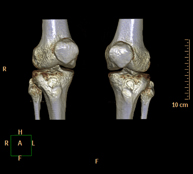

Exploració radiològica que mitjançant un sistema de raigs X i detectors que giren al voltant del pacient i que reconstrueixen les imatges per ordinador (TC Multidetector), permet l'estudi detallat de les articulacions sacroilíaques i descartar malalties inflamatòries, traumàtiques o degeneratives. - TC de genoll

Exploració radiològica que mitjançant un sistema de raigs X i detectors que giren al voltant del pacient i que reconstrueixen les imatges per ordinador (TC Multidetector), permet l'estudi detallat dels ossos, els músculs i les articulacions del genoll. - TC de turmell-peu